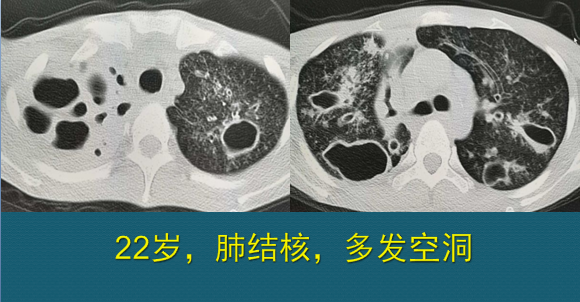

肺结核ct图片

48 两上肺空洞,斑块,条索,两肺支气管播散,树芽征---------提示肺结核